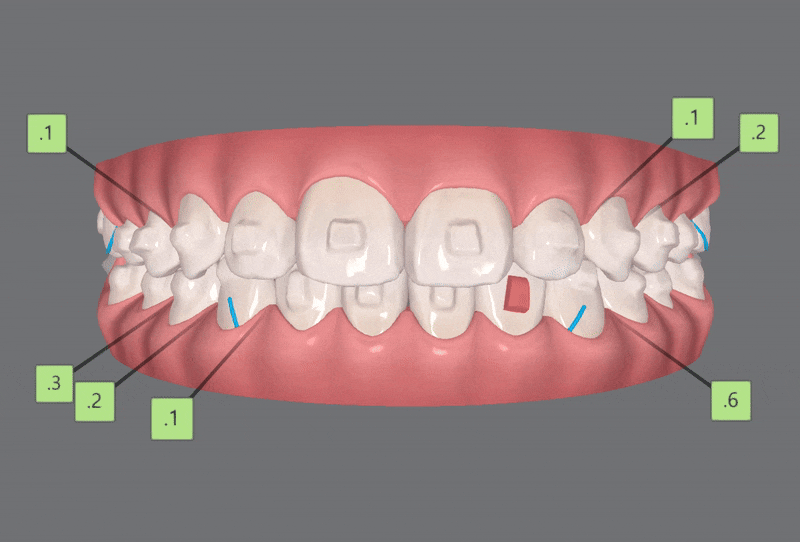

3rd ClinCheck(14개)

마지막으로 섬세한 디테일링을 위해

세번째 클린체크

(총 14개의 장치)를 진행해드렸습니다.

'인비절라인퍼스트'는

아이들의 유치와 영구치에

딱맞게 제작되고

5일~7일에 한번씩 새로운 장치로 갈아끼게 되므로 위생적입니다.

마지막 클린체크를 통해

교정이 마무리된 사진입니다 :)